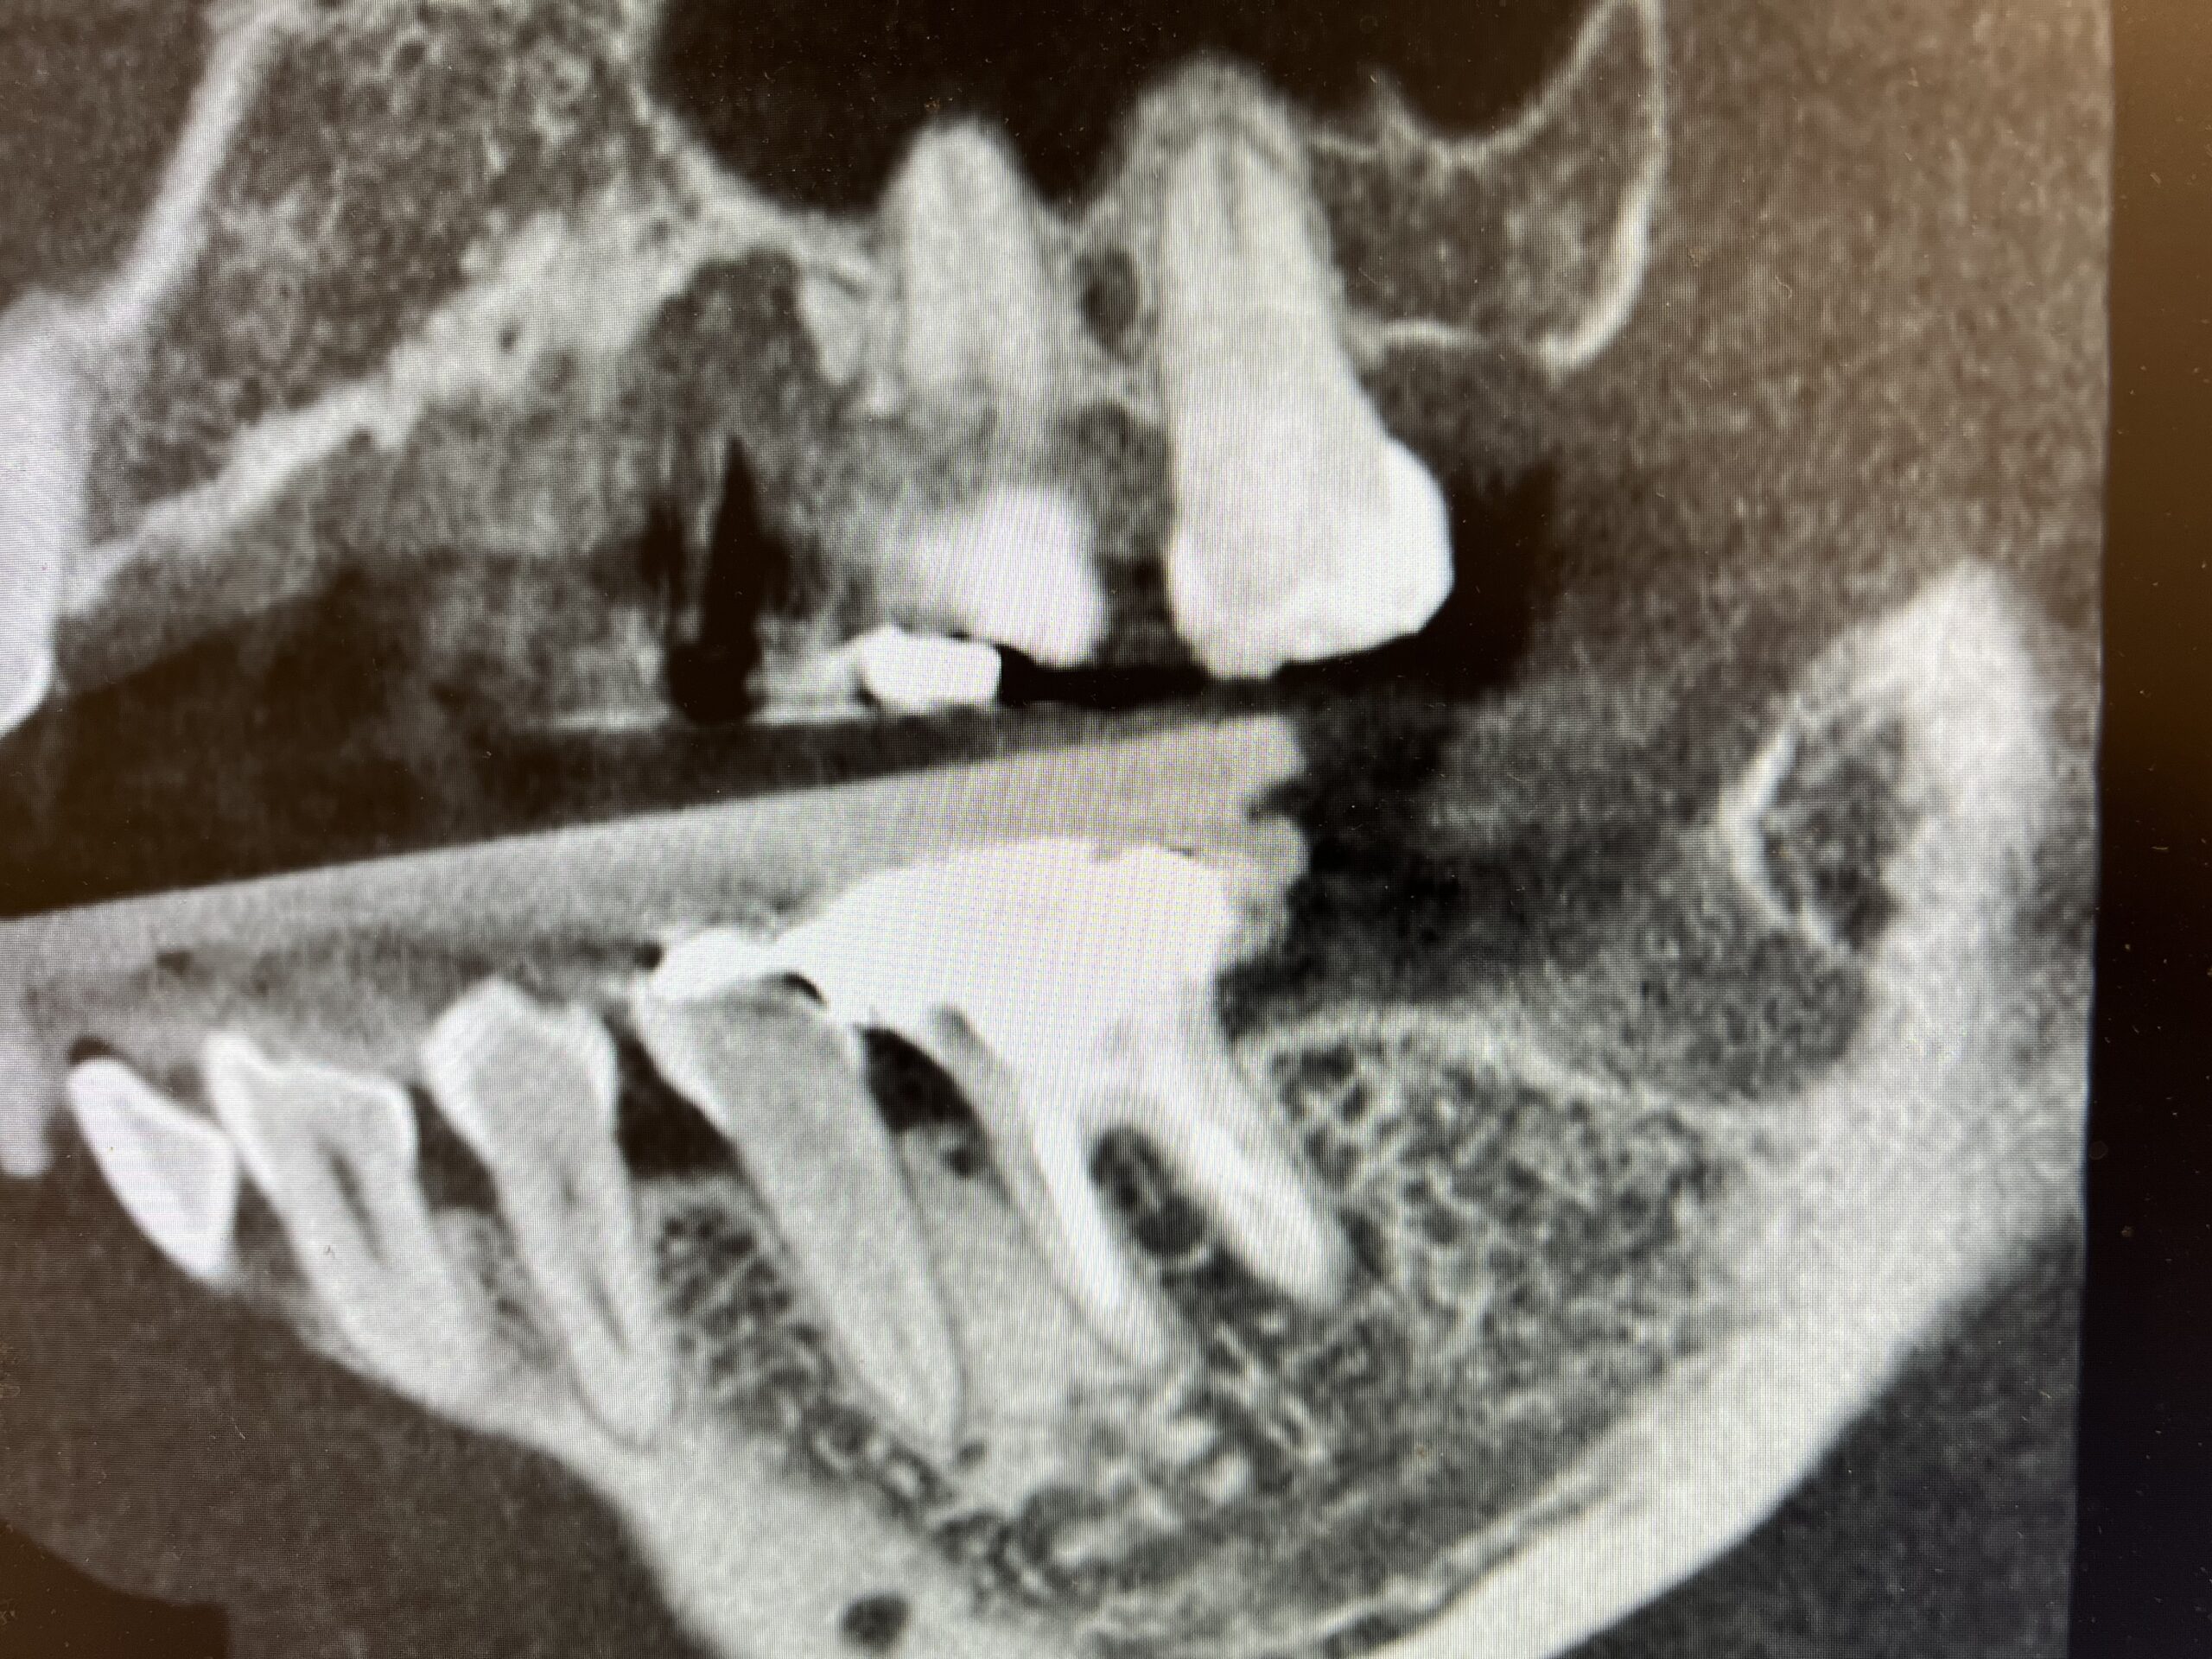

ヘビースモーカー重度歯周病患者のインプラント治療「口が臭う、歯ぐきが膿んでいる」本町・60代男性

症例情報

症状 「口の中、全体から臭いがする。定期的に歯ぐきが膿んでいて噛めない。歯周病だと思う。」 年齢・性別 60歳 男性 治療期間 5ヶ月 治療方法 インプラント治療 費用 術前シミュレーション5.5万円×2 インプラント治療49.5万円×2 デメリット・注意点 術後に出血、痛み、腫れが生じる可能性がありますが、2〜3日で落ち着きます。 -